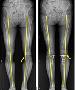

ÈØ´Ù¸® ³öµ×´õ´Ï °üÀý¿° À¯¹ß? °£´ÜÇÑ ¼ö¼ú·Î ±³Á¤ °¡´É

50´ë ÁֺΠȲ¸ð¾¾´Â ¾ó¸¶ ÀüºÎÅÍ ¹«¸­ÀÌ ½ÃÅ«°Å¸®°í ´Ù¸®°¡ ¹«°Å¿öÁ® °È±â°¡ ¹÷Â÷ º´¿øÀ» ã¾Ò´Ù. Ȳ¾¾´Â ¡®¹«¸­ °üÀýÀÇ OÀÚ º¯ÇüÀ¸·Î ÀÎÇÑ ÅðÇ༺ °üÀý¿°¡¯ Áø´ÜÀ» ¹Þ¾Ò´Ù. OÀÚ·Î ÈØ ´Ù¸®°¡ °üÀý¿°ÀÇ ¿øÀÎÀÌ µÆ´Ù´Â °ÍÀÌ´Ù. ¿¹ÀüºÎÅÍ ´Ù¸® ¸ð¾çÀÌ ÄÞÇ÷º½º¿´´Âµ¥, °üÀý..